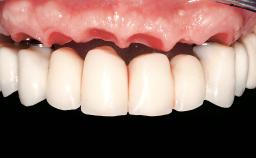

Immediate Loading of Eight Implants in the Maxilla and Six Implants in the Mandible and Final Restoration with Three-Unit and Four-Unit FDPs

Extensive scientific evidence has confirmed that immediately loaded implants with fixed full-arch provisional restorations can osseointegrate with success rates similar to conventionally or delayed loaded implants. A number of immediate-provisionalization techniques for edentulous jaws have been described. Some protocols differ when it comes to prefabricated provisional templates versus complete denture conversion; intrasurgical impressions versus direct relining; and cemented versus screw-retained provisional restorations. In this context, complete-denture conversion has been proposed for either intrasurgical impressions or direct relining. Another possibility is the utilization of a prefabricated provisional to be adapted either in the mouth (by direct relining) or in the laboratory (on a working model obtained from an intrasurgical impression).

Prosthesis Type FDP

SAC Level Complex

Defining Characteristics Fully edentulous upper jaw to be rehabilitated with an implant-borne fixed dental prosthesis

Loading Protocol Immediate

Retention Cemented, with prosthesis margin < 3mm submucosal Cemented, with prosthesis margin < 3mm submucosal

Esthetic Risk High

Provisional Implant-Supported Prosthesis Prosthodontic margin < 3 mm apical to mucosal crest Prosthodontic margin < 3 mm apical to mucosal crest